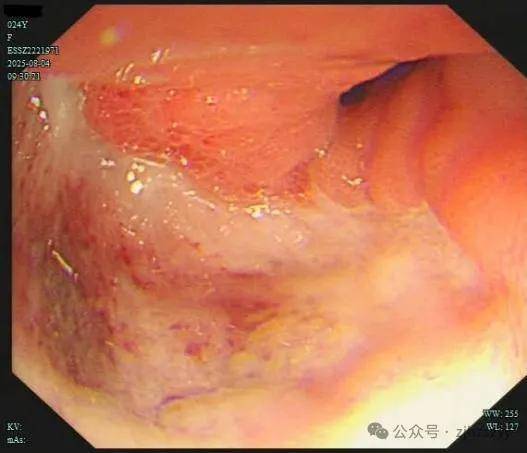

直到她开始频繁出现黑便,并在片场拍戏时几次呕血,才被同事紧急送往我院急诊。情况紧急,医生立即为小雯安排了急诊胃镜检查,发现她整个胃窦被一巨大的溃疡占据,黏膜组织变得僵硬、缺乏弹性,好似“皮革”一般。而随后的活检结果,更是给了这个年轻姑娘沉重一击——胃印戒细胞癌。